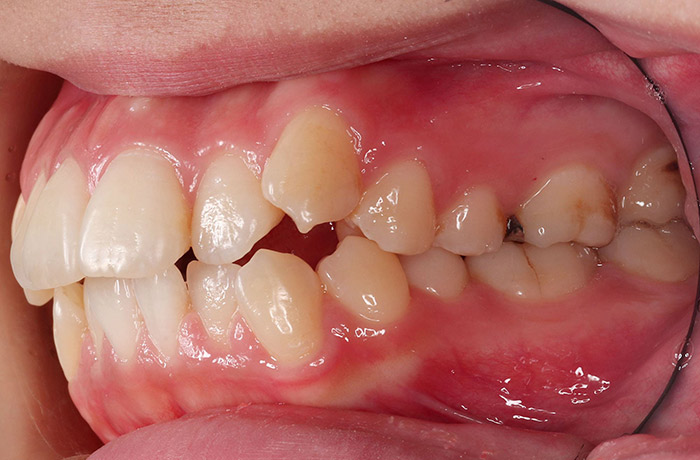

K様

治療前

年齢 27歳

性別 女性

治療名称 マウスピース型カスタムメイド矯正歯科装置(インビザライン)・コンプリヘンシブパッケージ(フルパッケージ)

総額治療費用 770,000円(税込10%) 金額備考 精密検査料・診断料 33,000円(税込10%)

治療期間 1年11か月 通院頻度など 40日ごと

1枚につき10日装着を指示しました。

治療内容

患者の症状 上顎前歯の前突、八重歯

治療方法 上下左右の第一小臼歯抜歯で、マウスピース型カスタムメイド矯正歯科装置による矯正

治療結果 上顎前歯の前突、八重歯が改善されました。

歯並びをより良くするために追加でアライナーを発注しました。

リスク/副作用 決められた時間装着する必要があります。